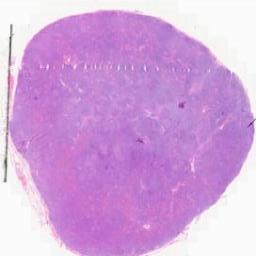

临床资料: 男,54岁,发现颈部两处肿物1年。双侧颈部局部探查:局部皮下软组织结构层次清晰,右侧颈部内可见一大小约24×8mm的淋巴结样回声,边界清,内回声不均匀血流信号,上述部位未见明显异常血流信号距体表约5mm。左侧颈部内可见数个淋巴结样回声,边界清,内回声不均匀,其中一个大小约6×5mm。CDFI:上述光团内及周边未见明感检查结果:双侧颈部软组织层异常占位(考虑淋巴结增大)。

大体所见: 灰白组织2枚,直径1.8-2.5cm,切面灰白。

免疫组化: 免疫组化:Ki-67(+),CD1O(+),CD20(+),Pax-5(+),CD3(+),CD5(+)。CD23(FDC网),Bcl-2(+),Bcl-6(+),MUM1(+),CD21(FDC网),CyclinD1(-),CD43(+),S-100(+),CD68(+).